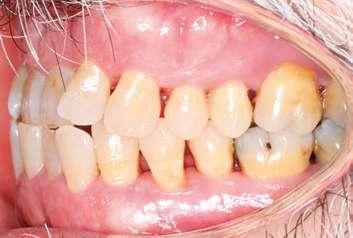

En el examen intraoral (Figura 1) se observó integridad de ambas arcadas, con excepción del 1.8, así como inflamación gingival, depósitos de biofilm generalizados, frémito a nivel del 3.4 y mordida cruzada anterior. Además, se observó la presencia de una migración dental patológica principalmente a nivel de los incisivos laterales y los caninos debido a la pérdida de soporte periodontal, lo que indica un estadio IV (Tonetti y Sanz 2019).

Figura 1. Vista general del examen intraoral en la visita basal.